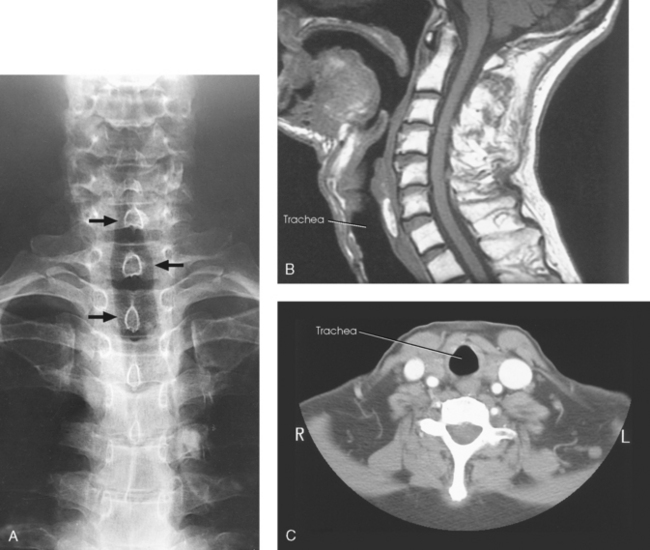

Structures shown: AP projection shows the outline of the air-filled trachea. Under normal conditions, the trachea is superimposed on the shadow of the cervical vertebrae (Fig. 10-22).

Fig. 10-22 A, AP trachea during inspiration showing air-filled trachea (arrows). CT and MRI are often used to evaluate the trachea and surrounding tissues. B, Sagittal MRI of neck. C, Axial CT of neck. (B and C, Modified from Kelley LL, Petersen CM: Sectional anatomy for imaging professionals, ed 2, St Louis, 2007, Mosby.)